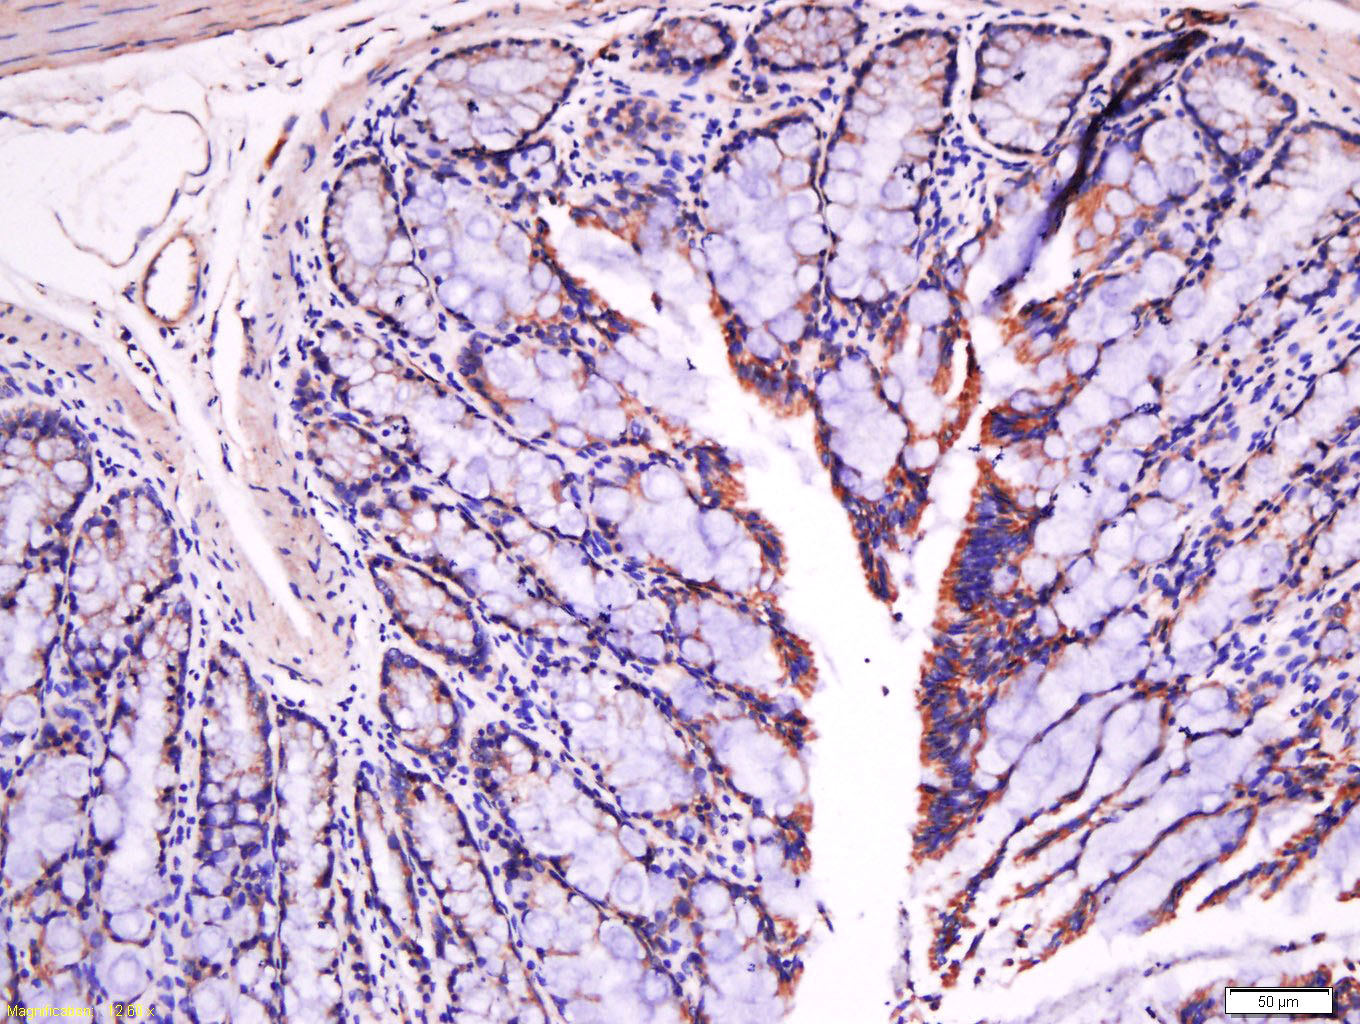

FaN(Fibronectin)是一种细胞粘附蛋白,参与细胞粘附,分化,移动,伤口愈合,凝血和机体防卫。主要分布于结缔组织及大部分基底膜上,作为判断良恶性上皮源性肿瘤(如乳腺癌等)的一个主要参考指标,亦可作为恶性肿瘤转移和病人预后的判断指标

This gene encodes fibronectin, a glycoprotein present in a soluble dimeric form in plasma, and in a dimeric or multimeric form at the cell surface and in extracellular matrix. Fibronectin is involved in cell adhesion and migration processes including embryogenesis, wound healing, blood coagulation, host defense, and metastasis. The gene has three regions subject to alternative splicing, with the potential to produce 20 different transcript variants. However, the full-length nature of some variants has not been determined. [provided by RefSeq, Jul 2008].

| IHC-P | Human, Mouse, Rat | Cow, Dog | 1:100-500 |